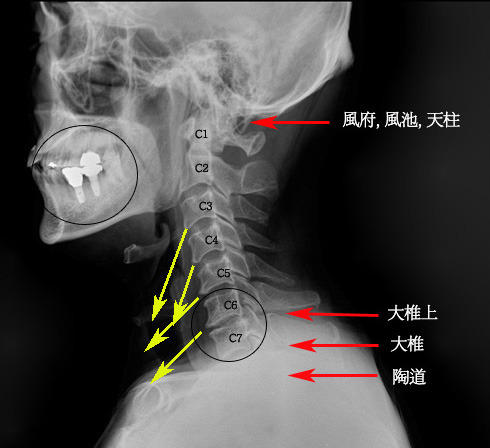

아래의 사진을 보시면서 설명을 이어나가도록 하겠습니다.  먼저 뼈를 살펴보면 C1 부터 C7 까지가 일자로 되어있는 것을 보실수 있습니다. 일자목이 되게되면 환자분이 젊은 나이의 경우에 별다른 통증을 못 느끼는 경우도 종종 있습니다만, 대체적으로 목과 어깨쪽의 불편한 증상을 느끼게 됩니다.

이런 경우에는 목을 일자상태에서 다시 C 자 커브를 이룰 수 있도록 교정해주는 작업이 필요하다 하겠는데, 침만으로 어떻게 증상이라도 완화하는 것을 기준으로 설명을 하도록 하겠습니다.

먼저 좌측의 노란 화살표에서 보시다시피, 경추에 붙어있는 근육들이 단축되어서 경추뼈에 골막을 형성하여, 뼈끝이 뾰족하게 변한 것을 보실 수 있습니다. 이러한 변화는 1-2년에 이뤄지는 것이 아니고 최소 수년에서 수십년에 걸쳐서 일어나는 변화입니다.

이 사진의 주요한 변증포인트는 일자목으로 인한 경항부의 불편함과 특히 C6-C7 의 협착으로 인한 어깨, 팔통증을 예측할 수 있습니다. C6 이 목경직과 상박부통증, C7 이 등쪽 통증을 수반하게 됩니다. 또한 신경의 체절분포에 따라 C6-7번 영역에 해당되는 부위의 병증이 나타납니다. 주로 어깨나 손가락의 저림, 감각이상등입니다.

다른 많은 방법들이 있겠습니다만, 이런 경우에 자침은 풍부, 풍지, 천주, 대추상, 대추, 도도, 거골, 견중, 곡지등을 자침하여야 함을 진단내릴 수 있습니다. 이런 협착증의 경우에 침치료 몇 회로 뼈가 자리를 잡아주지 않습니다. 오수혈을 쓰던 MPS 를 하던, 약침을 쓰던 어느 정도 효과를 볼 수 있을 것이나 시간적인 여유를 가지고 치료를 하셔야 증상의 개선을 볼 수 있을 것이며, 근본치료는 역시 교정이 가장 적합할 것입니다. 그러나 여기서는 침만으로 이야기 하려고 합니다. 적절한 한약투여와 침구치료를 한다면 2-3개월정도의 치료가 필요할것입니다. 아울러 보조적으로 경추교정용 베개를 구입하셔서 쓰시면 많은 도움이 됩니다.